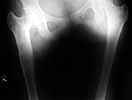

At present the problems to be dealt with were: coxa vara and femoral shortening (5cm) on the right side (Standing radiographs shown in pictures 02,03 and 04).